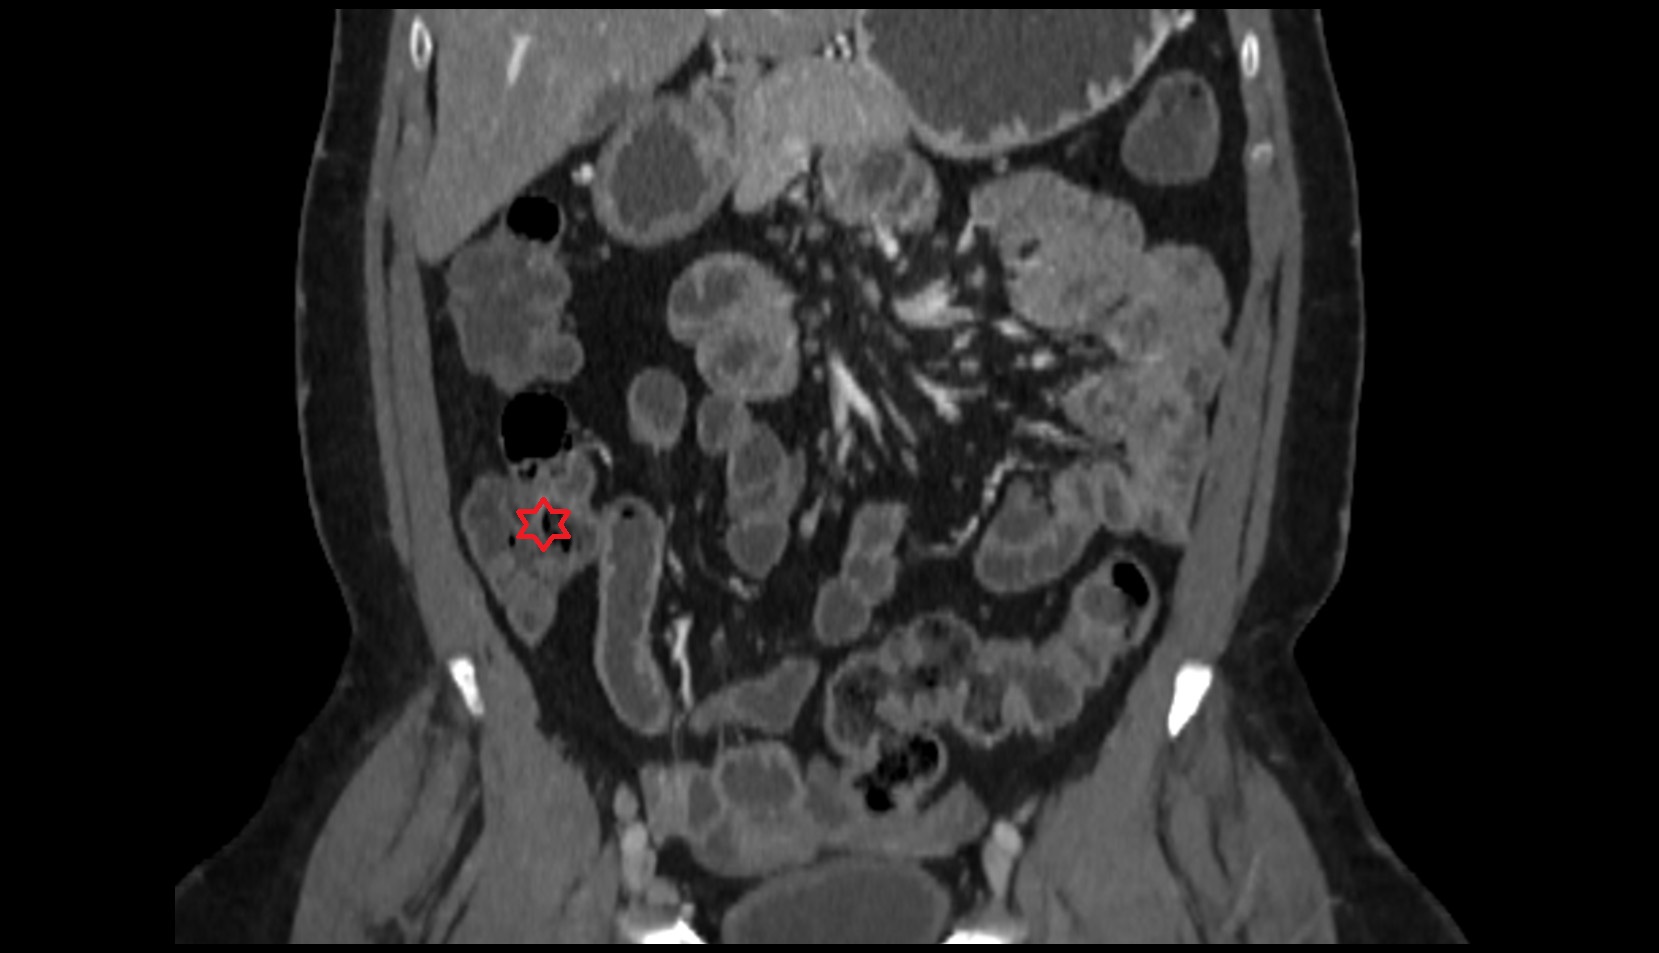

- Rectum

- Mesorectal fascia

- Mesorectum

- Mesorectal free fluid